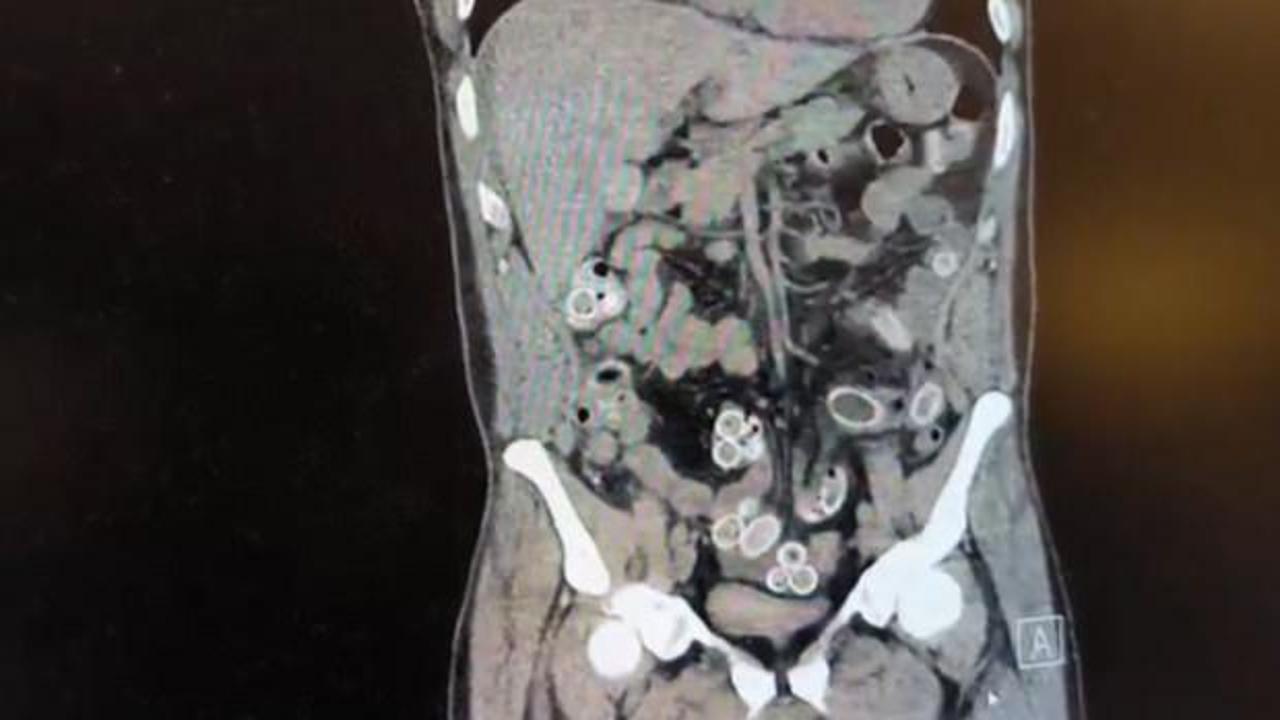

Fas’tan yaklaşık 3 bin kilometre uzaklıktan uçakla Türkiye’ye gelen Cüneyt G., 2 gün sonra karın ağrısı şikayetiyle Fulya’daki özel bir hastaneye başvurdu. Yapılan muayenenin ardından Cüneyt G.’nin tomografisi çekildi. Şüphelinin mide ve bağırsaklarında yabancı madde tespit edilmesi üzerine hastane yetkilileri durumu polis ekiplerine bildirdi.

İhbar üzerine çalışma başlatan Beşiktaş Asayiş Büro Amirliği ekipleri, doktorlarla görüşme gerçekleştirdi. Doktorların değerlendirmesi sonrası ameliyata alınan Cüneyt Ç.’nin bağırsaklarından, toplam ağırlığı 259,7 gram olduğu öğrenilen 49 esrar macunu çıkarıldı. Şüpheliye ait 1 adet cep telefonu da hastane yetkilileri tarafından polis ekiplerine teslim edildi.